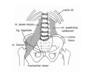

•Afgræns regio gluteali og anfør hvilke strukturer der kan ses og hvilke der kan palperes i regionen.

Regioglutealis:

opadtil: crista iliaca

fortil: forreste kant af m. gluteusmaximus

medialt: os sacrum

distalt: sulcus glutealis

svarer stort set til m. gluteusmaximus.

Afgræns regiocoxalisog anfør hvilke strukturer der kan ses og hvilke der kan palperes i regionen.

afgrænsning: forkanten af m. gluteusmaximus, crista iliaca og forkanten af m. tensor fasciae atae, nedadtil trocantermajor.

Muskelkanterne af m. gluteusmaximusog m. tensorfasciaelatae kan ses og palperes. Bagtil i regionen føles m. gluteus medius.

Angiv afgrænsningen af foramen ischiadicum majus.

Insicura ischiadicum major og lig. sacrospinale

•Angiv afgrænsningen af foramen ischiadicum minus.

lig. sacrotuberale og lig. sacrospinale samt incisuraischiadicaminor.